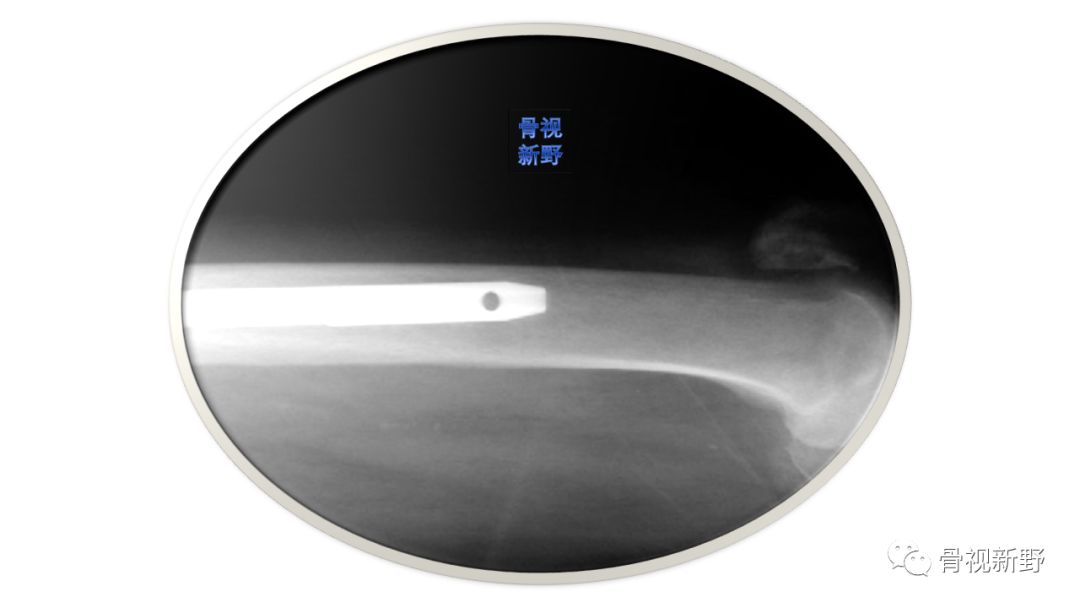

经大转子尖的主钉,进钉点应略偏内

软组织、巾单等的影响及反复的髓扩插入、扩髓,易致入口逐渐偏外扩大,这样可导致偏外置钉,由此导致骨折近端内翻、头钉偏高。因此,建议紧挨大转子尖内侧进针。在透视下,髓扩能完全包括在近端股骨皮质内,再开始小心扩髓,这样可避免偏外置钉。